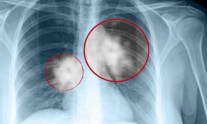

ΕΕ: Έγκριση νέας ανοσοθεραπείας για τον καρκίνο του πνεύμονα και της κύστης

Το πράσινο φως για την κυκλοφορία μιας νέας ανοσοθεραπείας για τον προχωρημένο καρκίνο του πνεύμονα και της ουροδόχου κύστεως...